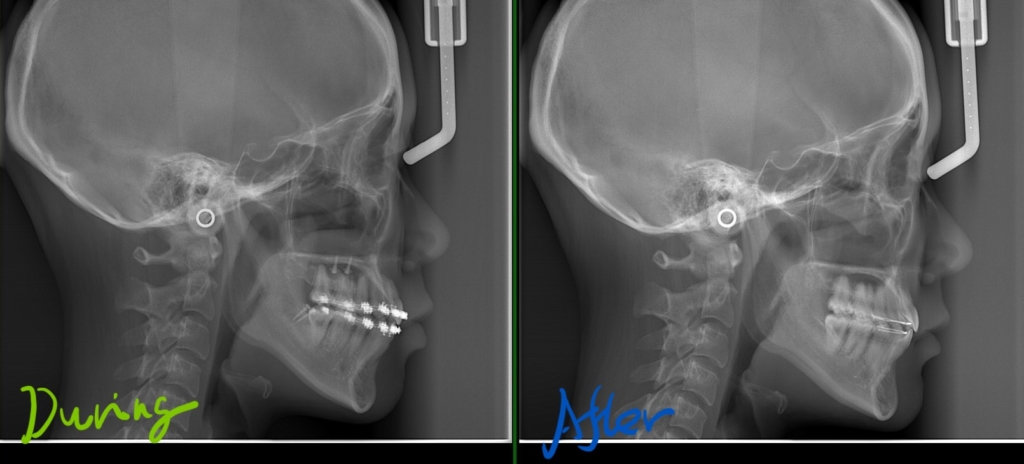

そこで今回は、もう少し引っ込ませたい分をアンカースクリューを併用して歯列を丸ごと後方へ移動させ(引っ込ませて)、口元をもっとスッキリと変化させよう!という治療プランを実行することにしました。

上顎の真ん中(口蓋部分)と、下顎の智歯を抜いた跡に、アンカースクリューを植立しました。

上顎ではPLASとパラタルバーを利用して、下顎では直接、各々アンカースクリューから力を加えて、上下の歯列全体をさらに奥へ引っ込ませるべく、治療を進めました。

【After】

矯正後の状態をレントゲン写真で確認すると、

今回の治療を振り返り、

抜歯スペース分だけを利用した八重歯などを治してだけでは、歯並びはきれいになったけれども、口元の変化は今一つでした。

しかし、上下の歯列をさらに奥へ移動させることで、口元を更に変化させることが出来ました。

その変化をレントゲン写真で追ってみましょう。

治療期間も延びて患者さんも大変だったとは思いますが、アンカースクリューを上手く使うことで、満足のいく結果になったのではないかと思っています。 ご苦労様でした。。。